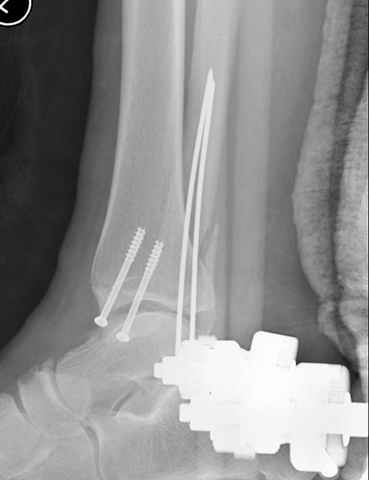

A propos fibular fixation if one is eager to stabilize it separately. In the fracture pattern a way of closed fixation by V-shaped stressed wire (advanced by colleagues from Moscow, prof. Lazarev A.F. et al.) must be excellent. We use indirect closed reduction by the external fixator. Example attached, that fibular fracture is even more suitable for plating but the wire did the job.

Еще, кстати, о фиксации лодыжки, если уж непременно хочется ее отдельно стабилизировать - при таком характере перелома замечательно должен сработать предложенный проф. Лазаревым с соратниками способ фиксации напряженной V-образной спицей. Опять же, открытая репозиция не нужна, мы делаем непрямую репозицию именно аппаратом. В приложении пример, там перелом малоберцовой куда менее поперечный, чем в данном случае, но все равно получилось закрыто без пластинки.